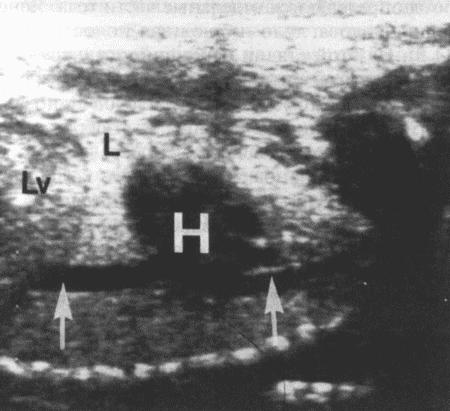

Фиг. 11.7.

Ультразвуковое изображение грудной полости плода, демонстрирующее сердце (Н), печень (Lv), легкие (L) и крупные сосуды (стрелки). Датчик на 7,5 МГц, шкала в см